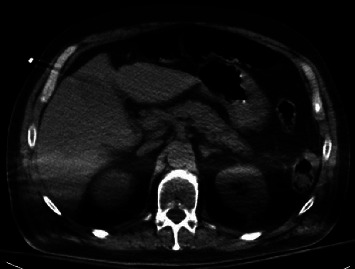

我们报告了一个病例,一名 62 岁的男子因摔倒和精神状态改变而被紧急医疗服务人员送来。他被发现患有严重的高钾血症、急性肾损伤和横纹肌溶解症。高钾血症用聚苯乙烯磺酸钠(SPS)治疗。住院期间,他目睹了黑色柏油样粪便和血红蛋白的显著下降。内镜检查显示,他的胃部有不出血的大面积弥漫性溃疡,并有近期出血的痕迹,溃疡活检结果显示与 SPS 引起的胃溃疡一致。局部没有发现其他出血源,这表明急性上消化道出血是由 SPS 粘膜损伤引起的。

We report a case of a 62-year-old man who was brought in by emergency medical services after a fall and change in mental status. He was found to have severe hyperkalemia, acute kidney injury, and rhabdomyolysis. The hyperkalemia was treated with sodium polystyrene sulfonate (SPS). During hospitalization, he witnessed having black tarry stools along with a significant drop in hemoglobin. Endoscopic evaluation demonstrated nonbleeding large diffuse gastric ulcers with stigmata of recent bleeding, and ulcer biopsy revealed findings consistent with SPS-induced gastric ulceration. No other source of bleeding was localized, suggesting acute upper gastrointestinal bleeding due to SPS mucosal injury.